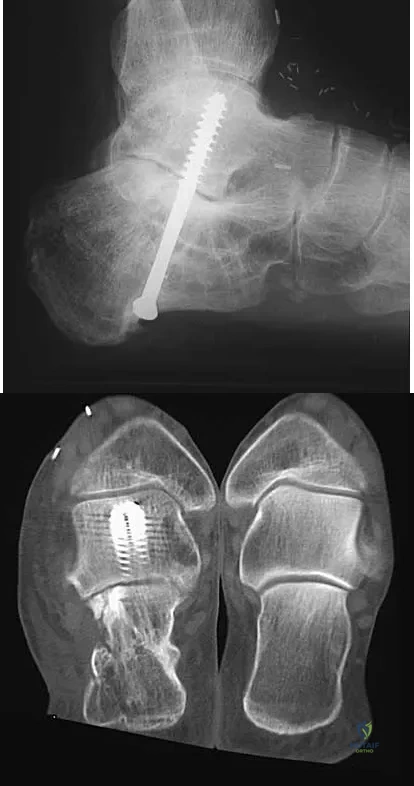

A 45-year-old man has persistent hindfoot pain that is aggravated by weight-bearing activities. History reveals that he sustained a calcaneus fracture 2 years ago, and he underwent a subtalar fusion 1 year ago. Examination reveals tenderness in the sinus tarsi and across the transverse tarsal joint. A plain radiograph and a CT scan are shown in Figures 24a and 24b. A technetium Tc 99m bone scan reveals uptake at the subtalar joint and at the transverse tarsal joints. Management should now consist of